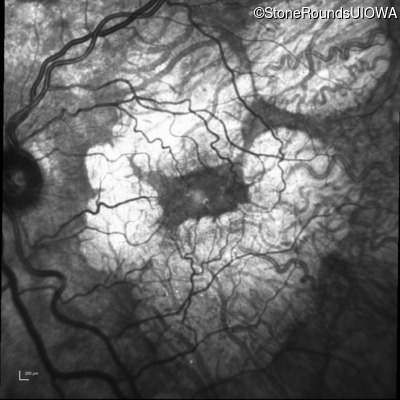

Age at visit: 51 years

This 51 year old woman first experienced some abnormality in her distance vision when she was 27 years old. She feels that her vision has been stable since that time.

Diagnosis & molecular findings

AR Stargardt Disease ABCA4 Gly1507Arg GGG>AGG IVS42+1 G>A AR